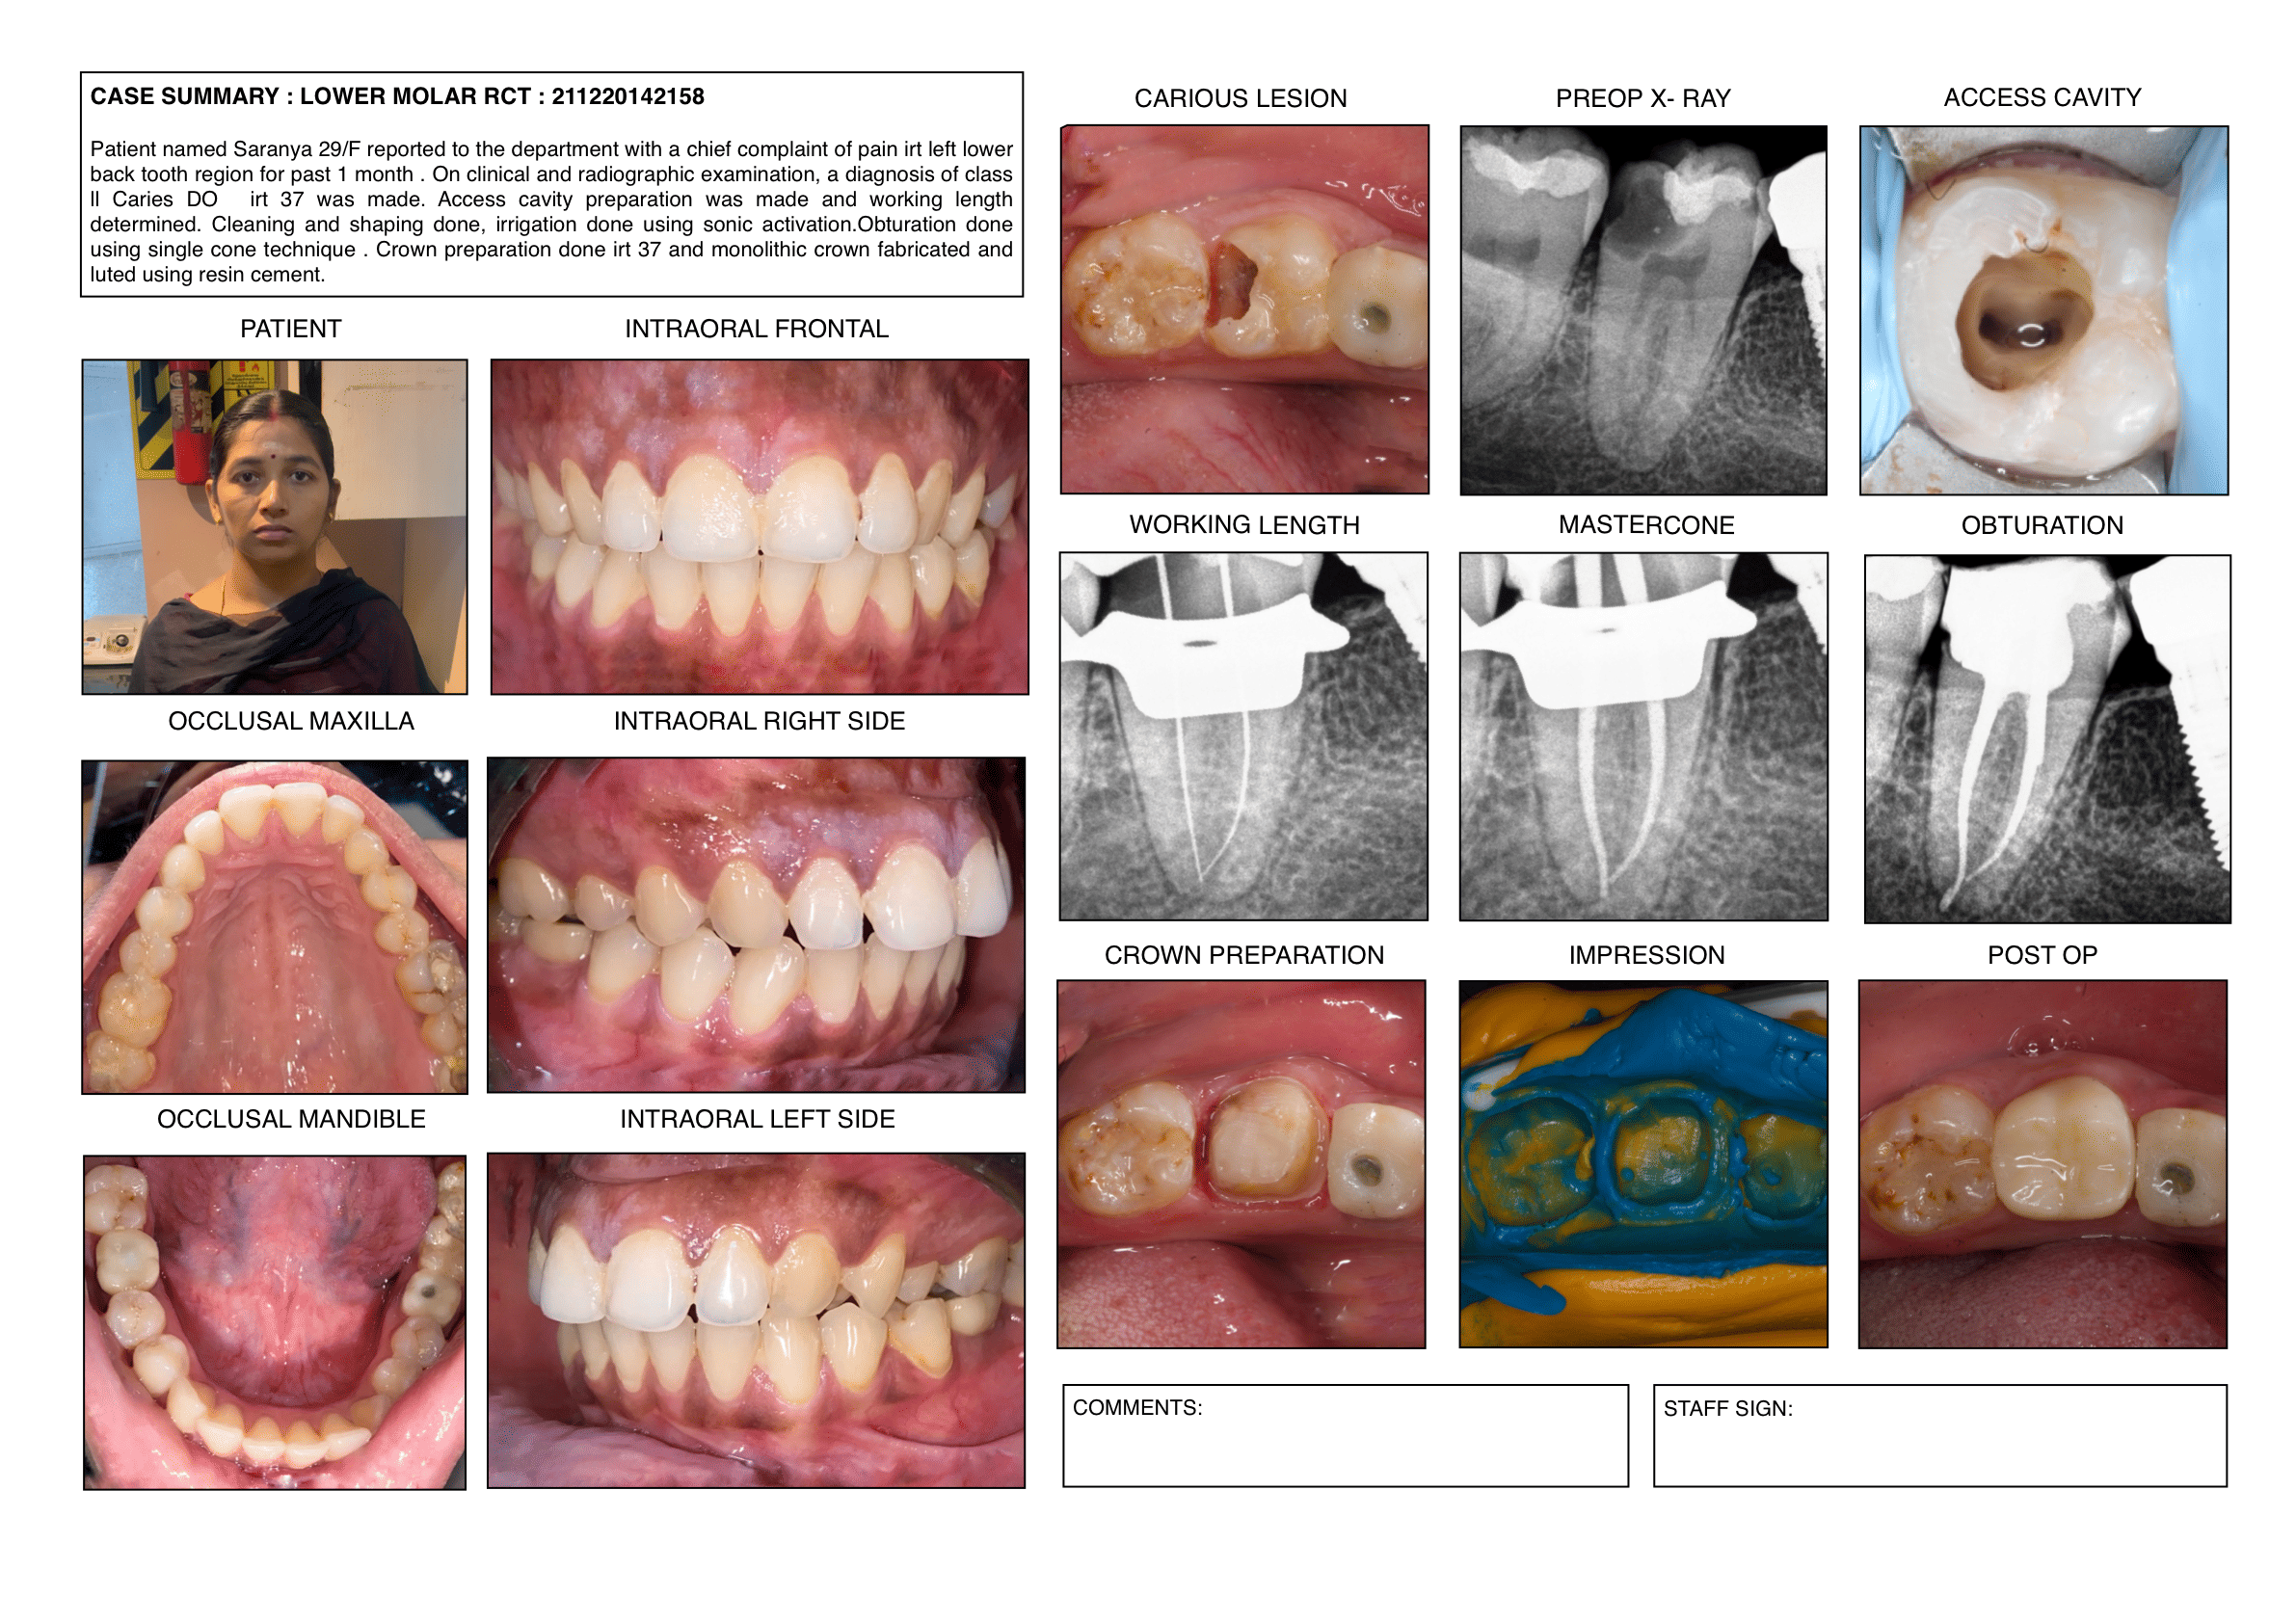

Endodontic cases